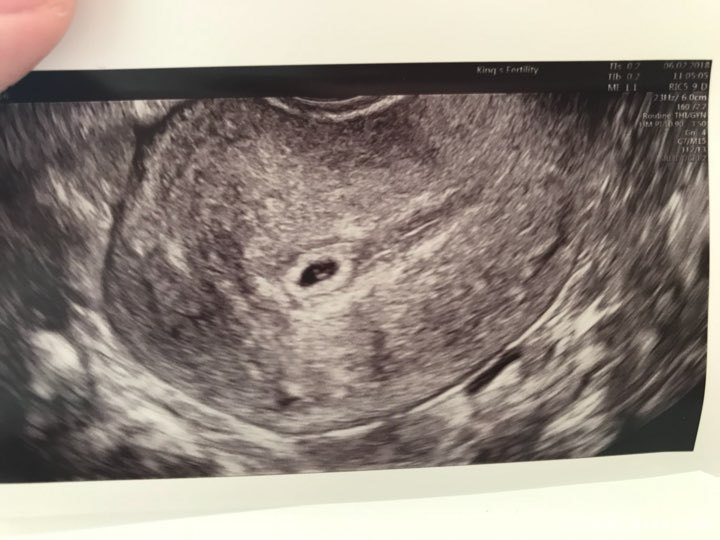

前期hcg翻倍不太好,大概才60%,加上前两天擦拭有褐色渣状物,便央求医生帮我提前看看。

因为是加插的,而且时间还较早,医生说只能告诉我宫内孕,可以看见卵黄囊,但不准备仔细往下看了,让我等到七周再来做一超。我再三询问能否看到出血点,医生又快速瞟了一眼说没有,她估计可能是宫颈引起的出血。说完就赶我出来了。[微笑]

有懂看B超图的姐妹帮我看看还能看到什么信息吗?谢谢![鼓掌][鼓掌][鼓掌]